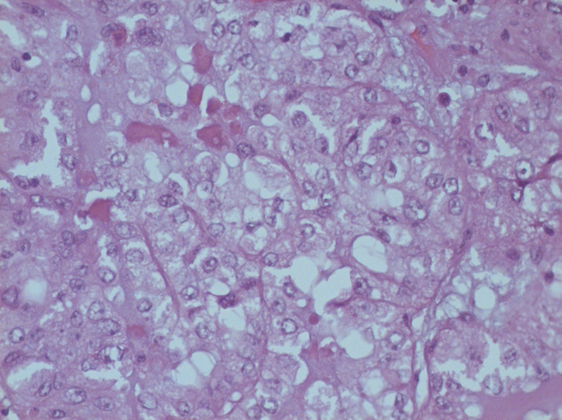

El resultado histopatológico del tejido resecado fue el de un tumor mülleriano de tipo adenocarcinoma de células claras el cual presentaba en la inmunohistoquímica positividad para CK7, AMCAR y PAX 8, y negativo para CK20 y Uroplaskinll (Imagen 4).

Imagen 4 Fotografía microscópica mostrando células con abundante citoplasma claro y pleomorfismo nuclear

El papel de los marcadores de inmunohistoquímica es importante para el diagnóstico en caso de una posible afección directa por un adenocarcinoma del aparto ginecológico,11 debido a que los adenocarcinomas de células claras del aparato urinario usualmente presentan positividad para CK7, CEA, CA125 y expresión nuclear de p53, en ocasiones también para CK20, PAX-2, PAX-8 y AMCAR, estos siendo negativos para PSA, ER y PR. La variante histológica de adenocarcinoma de células claras conlleva un mejor pronóstico comparado con el carcinoma de células transicionales y de células escamosas, con una menor tasa de muerte por metástasis, siendo del 7% para el adenocarcinoma, y del 33% y 50% para el de células transicionales y escamosas, respectivamente.7